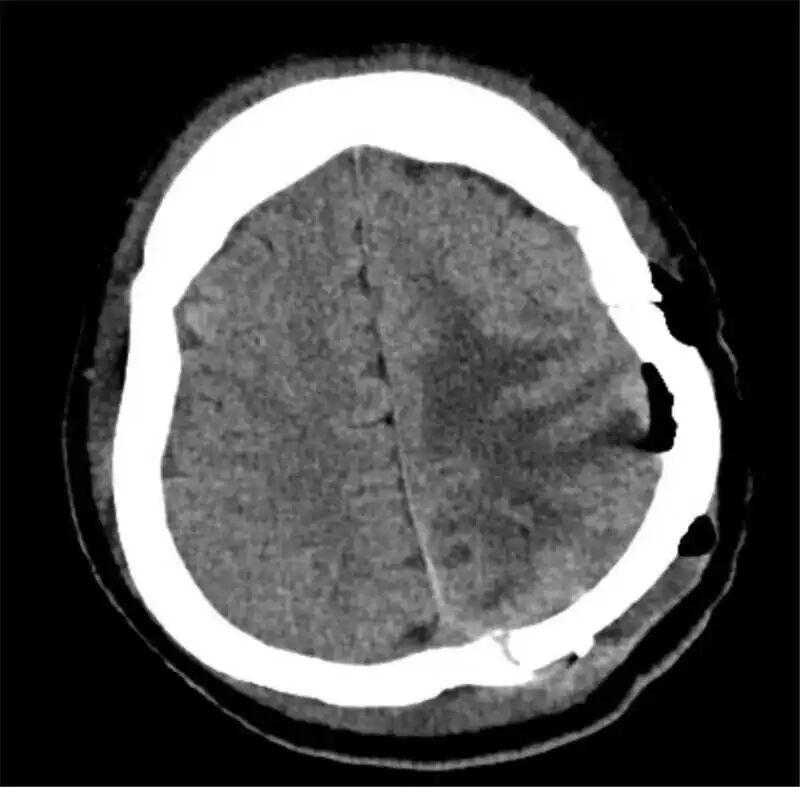

67岁的谢奶奶,则面临着一枚脑血管内的“不定时炸弹”——大脑中动脉瘤。与传统的开颅手术不同,团队此次采用先进的介入技术——WEB装置植入术,巧妙地为患者拆除了血管内的隐患。尤为重要的是,该技术避免了患者术后长期服用抗双抗药物,极大提升了患者的生活质量与安全性,真正实现了微创、高效、高质量的现代治疗目标。